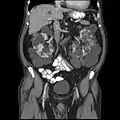

Adult polycystic kidney

Abdominal CT scan of an adult with autosomal dominant polycystic kidney disease: Extensive cyst formation is seen over both kidneys, with a few cysts in the liver, as well. (Coronal plane)